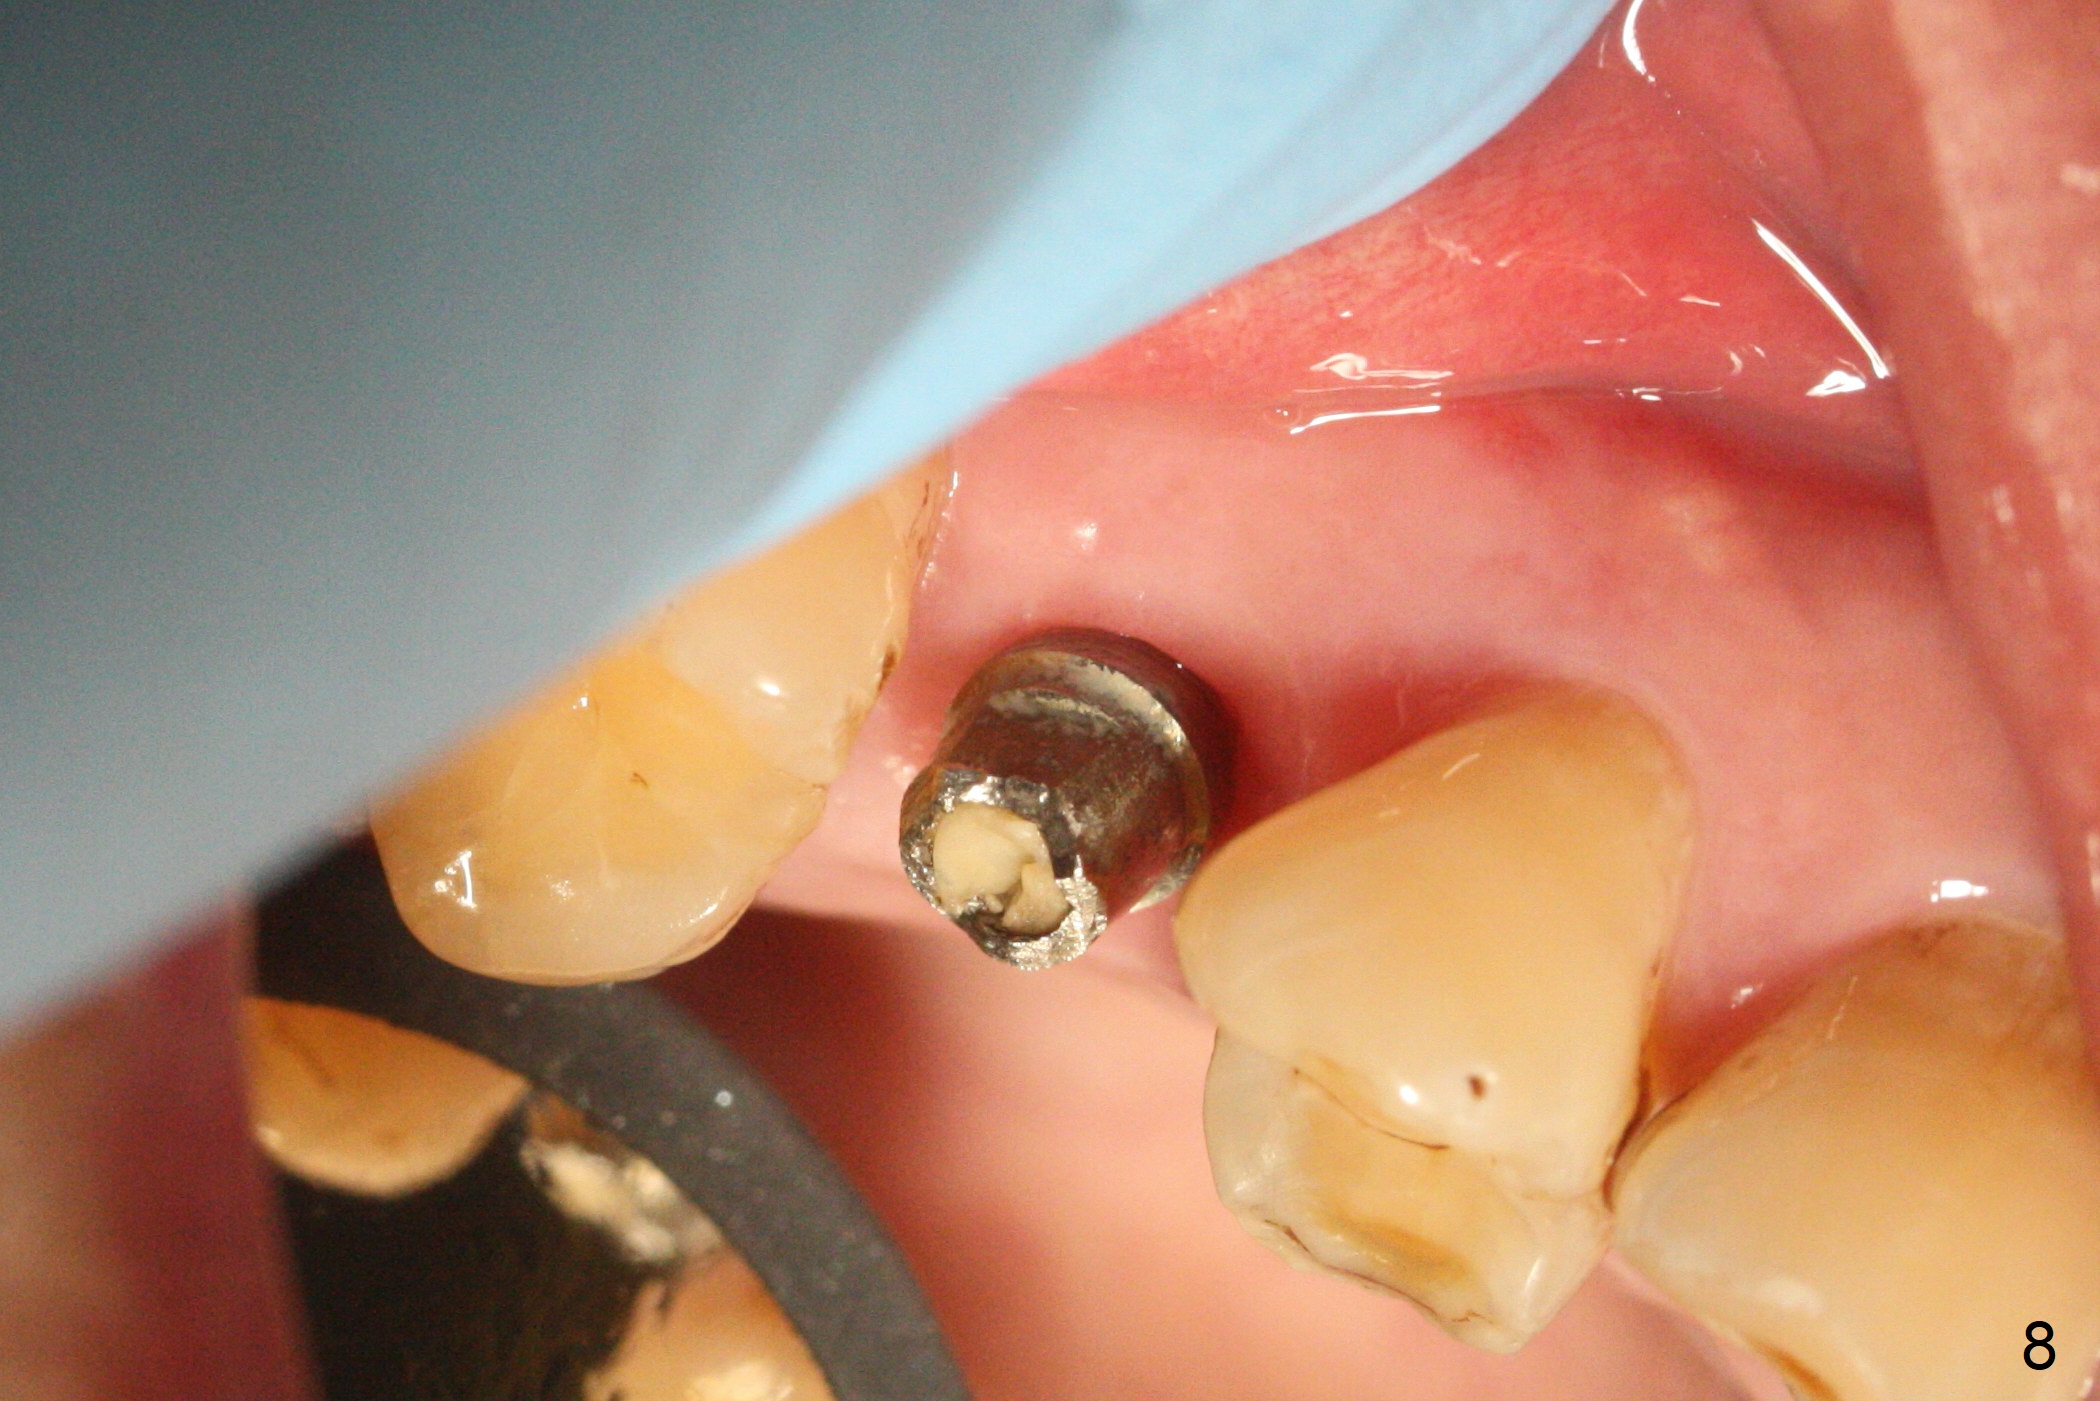

A 47-year-old man returns emergently with subgingival fracture of the lingual (L) cusp of the tooth #4 (Fig.1-3).  After extraction (no bony defect) without drilling, a 4x11 mm dummy implant is placed as a tap drill with satisfactory stability (Fig.4,5).  To get subcrestal placement, a shorter (4x9 mm) implant is inserted with insertion torque of < 35 Ncm.  In retrospect, a larger implant (4.5 mm) would be better in term of primary stability.  After allograft placement into the buccal and lingual gaps, a 4.5x4(4) mm abutment is placed for an immediate provisional.  There is a peri-implant gap 7 months postop (Fig.7<, as compared to the implant at #2 (6 months postop)) .  When the loose abutment is being retightened, the patient feels pain, although the gingiva appears healthy (Fig.8).  A larger implant should have been used; the abutment should have been removed.  The implant dislodges while the abutment is untightened 8 months postop.  The osteotomy is found intact.  A 4.5x11 mm dummy implant is placed 2 mm subgingival with 20 Ncm (Fig.9).  When a 4.5x11 mm definitive implant is placed 3 mm subgingival (Fig.10,11), torque reaches 50 Ncm.  A 5.5x3 mm healing abutment is placed.  Three months postop, the implant is stable (Fig.12,13) and impression is taken.